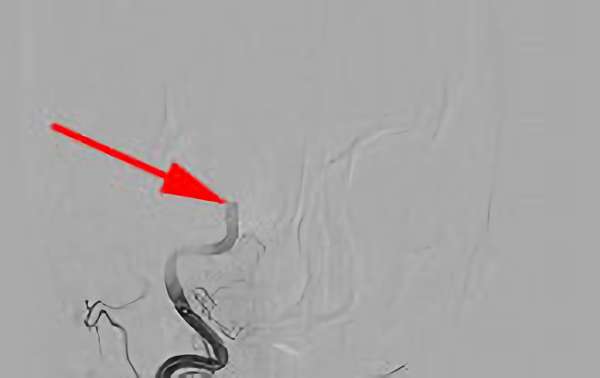

582

'19年7月27日

心原性脳塞栓症

50代

院内外来

中